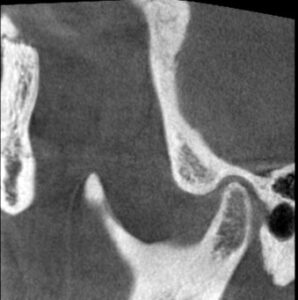

この状態になった時のこの患者さんのCTスキャンの比較はこちらです。

治療前 左側

治療後 左側

関節圧迫が取れているのがわかるでしょうか?

これが治療後の状態です。

赤い線は耳の穴です。

顎関節は耳の穴の裏側に位置します。

耳の穴を関節が圧迫していたらどうなりますか?